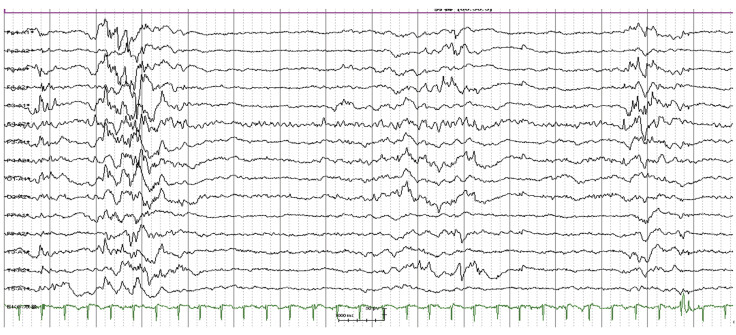

Results: Seizures and burst-suppression pattern were detected on the aEEG. The background belonged to discontinuous voltage, and showed discontinuity of cerebral activity in the form of the burst-suppression pattern. The classification of SWC in this record belonged to the "No SWC" category, which meant the child had severe brain damage. A typical neonatal single seizure was found. The seizure activity lasted approximately 30 seconds. However, clinical symptoms were not observed.